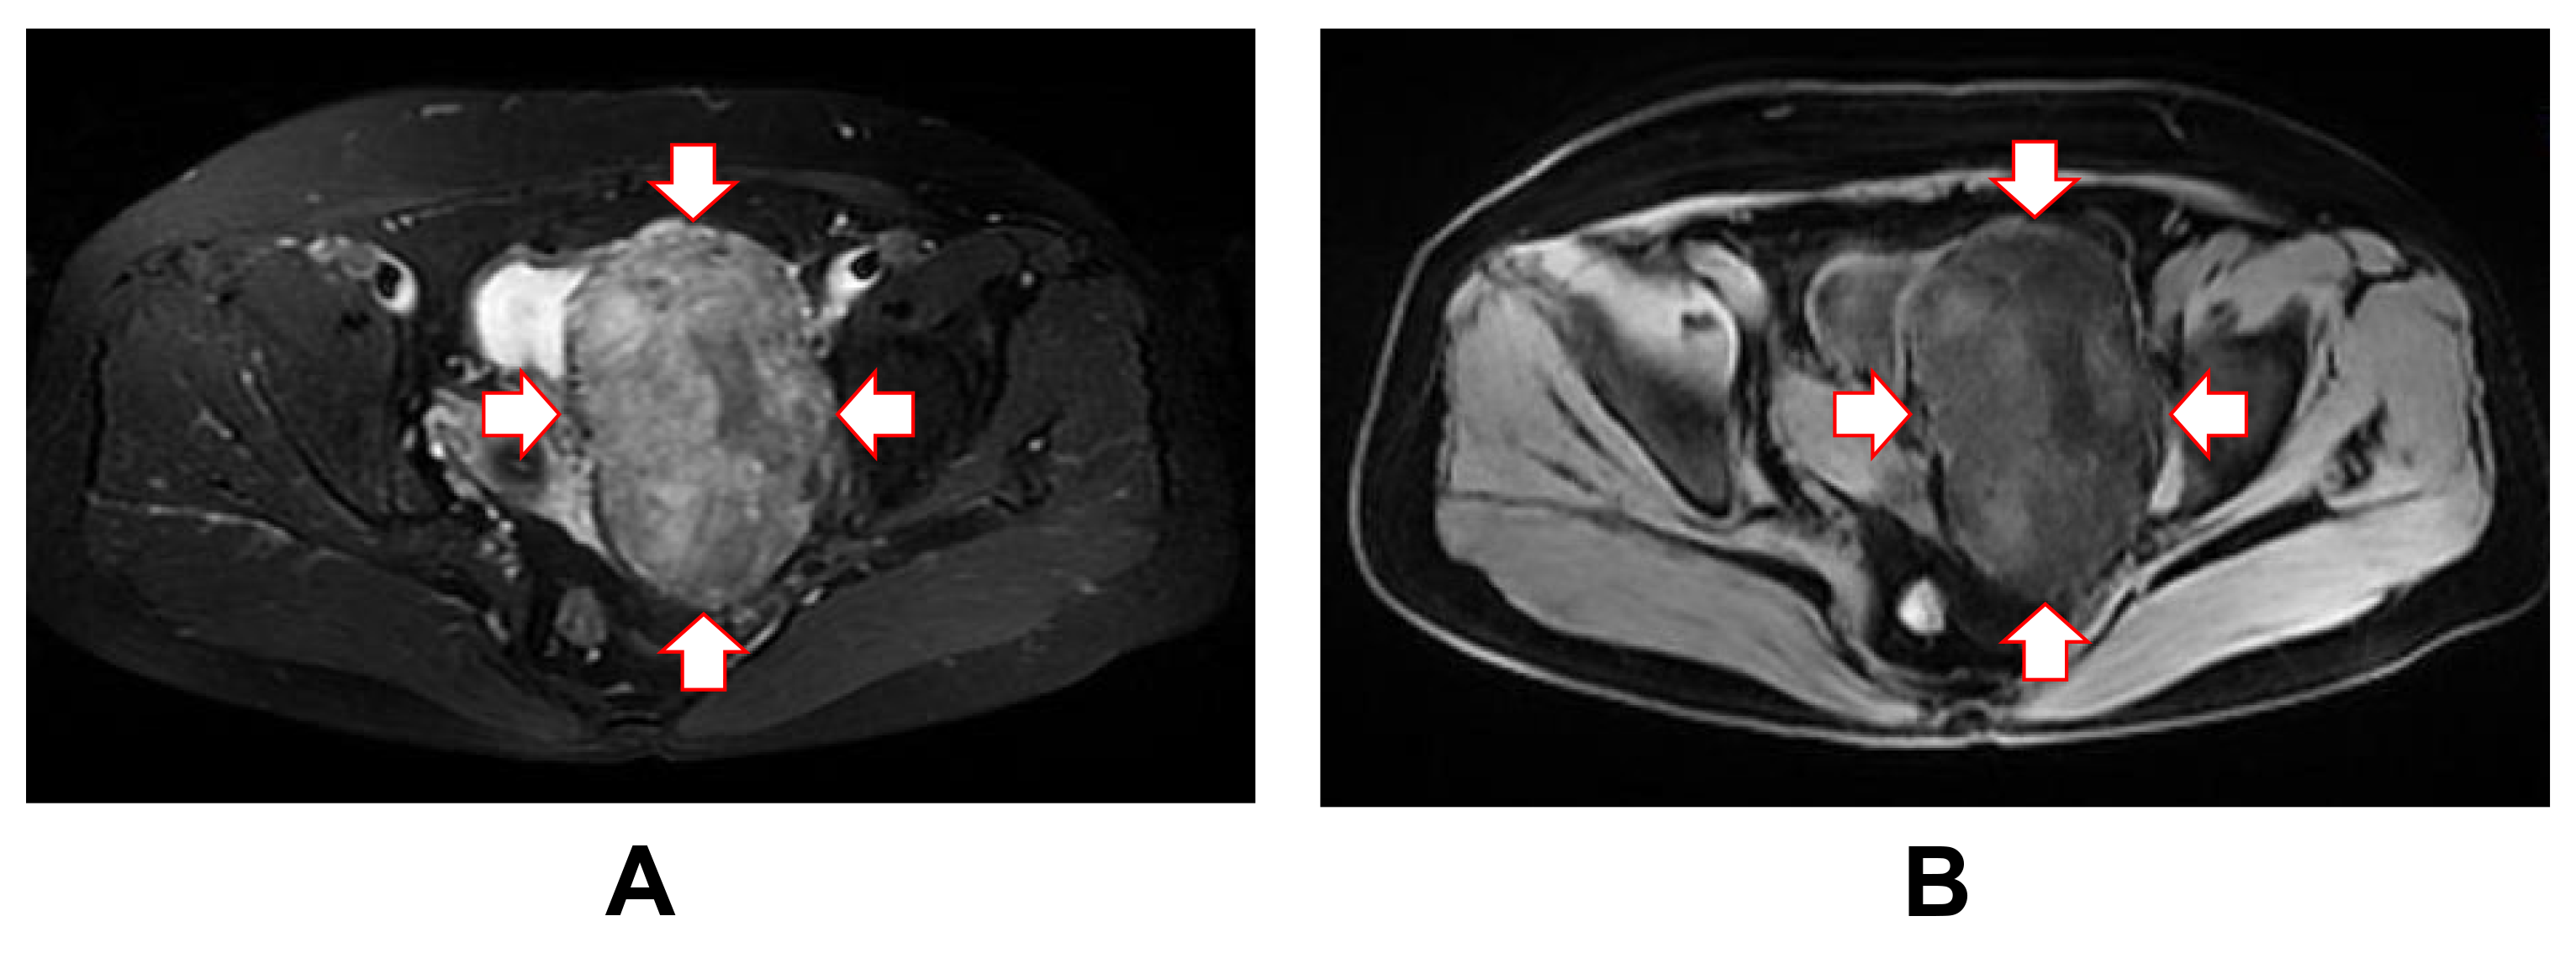

Fig. 1. Magnetic resonance imaging of the lesion mass. Magnetic resonance imaging showing a well-defined, deep mass in the left adnexal area on axial T1-weighted imaging (A) and T2-weighted imaging (B). T1, longitudinal relaxation time; T2, transverse relaxation time. Red arrows mark the boundaries of the tumor mass.

The diagnosis of SFT can be quite challenging due to its rarity, requiring an integrated approach that includes specific clinical, histological, IHC and even molecular findings. Combining the location of the mass with imaging findings, an ovarian sex cord-stromal tumor (thecoma) was initially considered by our radiologists. When MRI images are reviewed retrospectively, as in the present case, the fatty and hypervascular components of fat-forming SFT become very apparent, since the T1-weighted images make the fat appear bright (Fig. 1A). This may lead to a broader differential diagnosis that includes rarer lipomatous lesions such as angiomyolipoma and liposarcoma. Currently, a diagnosis of fat-forming SFT can be made by combining histological characteristics with IHC staining results. Histologically, most fat-forming SFTs resemble the cellular form of SFT, except for the presence of mature, non-atypical adipocytes. A combination of CD34, CD99 and BCL-2 IHC staining has traditionally been used to diagnose fat-forming SFT. However, although these IHC markers are sensitive, they are not sufficiently specific to distinguish fat-forming SFT from other pathological entities. STAT6 has emerged as a highly sensitive and specific IHC marker, with most SFTs demonstrating diffuse and strong nuclear expression [57]. Further studies and recently published case reports have confirmed the utility of STAT6 IHC staining in the diagnosis of fat-forming SFTs [58]. Moreover, the detection of NAB2-STAT6 fusion genes can help with the diagnosis of fat-forming SFT, since these are a hallmark of SFTs [37]. In the present case, tumor cells in the specimen were diffusely stained for STAT6. However, a limitation of our case report is that we did not perform NAB2-STAT6 fusion gene detection. In addition to STAT6, a recent study using next-generation sequencing revealed that several other genes, including peroxisome proliferator activated receptor-